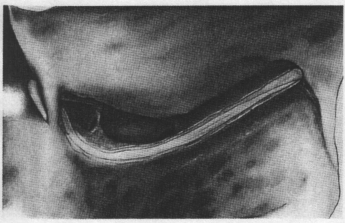

Разрезаются оболочки ЛН с помощью ножа Beaver вдоль направления его волокон (рис. 40, 41).

|